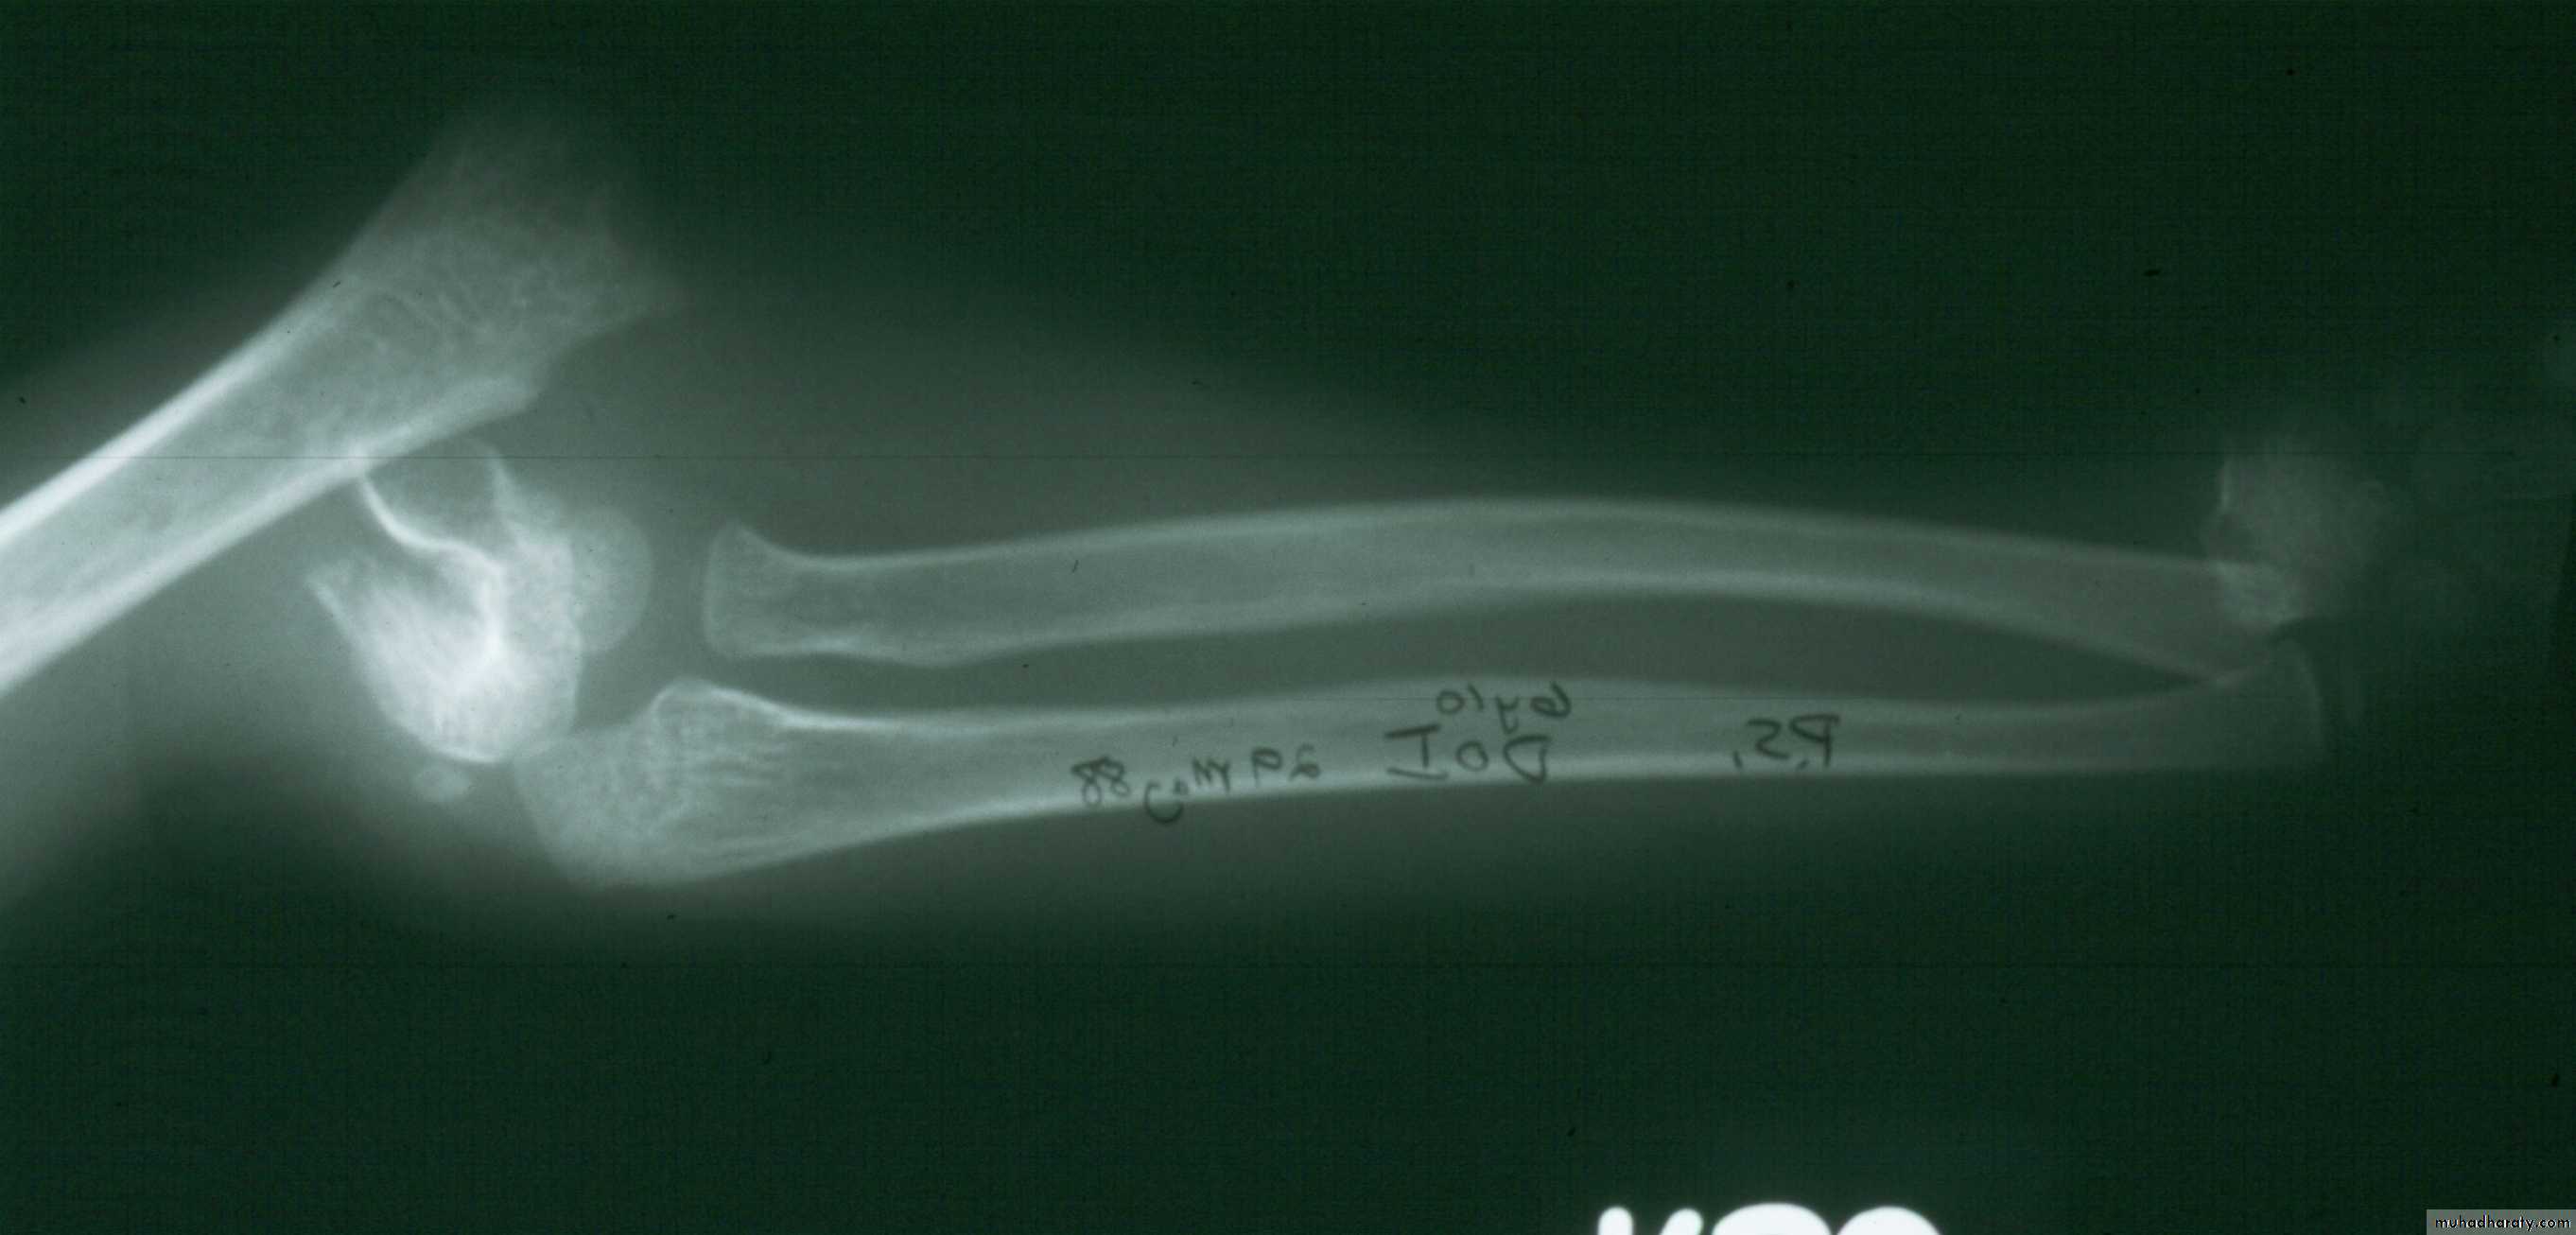

With the elbow in extension, align the distal fragment

to the proximal fragment in the coronal plane.1. Correct coronal plane alignment

2. Re-establish Length

TractionCounter-Traction

This usually requiresan assistant.

3.Correct Angulation

andPosterior Displacement

Apply longitudinal traction

with the elbow semi- flexed,while applying posterior

pressure on the proximal fragment.

Then, slowly flex the elbow to bring

the distal fragment into alignment.4. Temporary stabilization and assessment